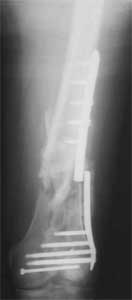

Attached are few examples from our Hospital:

B. Fixation loosening: distal cutting of the nail, non-unions do happen (cases attached).

Locking Plating has more distal screws than any nail, fixed angles and provides much better fixation, especially in osteoporotic bone.